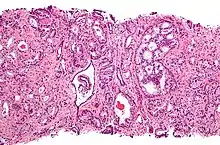

Gleason score 6 (3+3)

Cribriform pattern: Gleason grade 4

Gleason score 7 (3+4) with minor component of cribriform glands

Gleason score 8 (4+4) with glomeruloid glands

Gleason 4

Gleason pattern 4 glands are no longer single/separated glands like those seen in patterns 1-3. They look fused together, difficult to distinguish, with rare lumen formation vs Gleason 1-3 which usually all have open lumens (spaces) within the glands, or can be cribriform-(resembling the cribriform plate/similar to a sieve: an item with many perforations). Fused glands are chains, nests, or groups of glands that are no longer entirely separated by stroma-(connective tissue that normally separates individual glands in this case). Fused glands contain occasional stroma giving the appearance of "partial" separation of the glands. Due to this partial separation, fused glands sometimes have a scalloped (think looking at a slice of bread with bite taken out of it) appearance at their edges.[4][7]